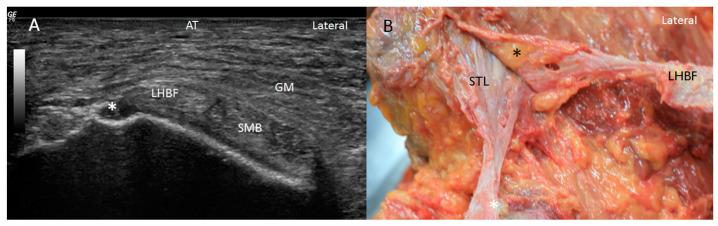

The proximal attachment of the hamstring muscles presents a hyperechogenic line surrounding the origin of the semimembranosus and the long head of the biceps femoris muscles, as well as another hyperechogenic line covering the sciatic nerve. The anatomical and histological study confirms the ultrasound results and shows different layers forming the sacrotuberous ligament. Furthermore, it shows that the proximal attachment of the semimembranosus muscle has a more proximal origin than the rest of the hamstring muscles. Moreover, this muscle shares fibers with the long head of the biceps femoris muscle and expands to the adductor magnus muscle. The histological analysis also shows the dense connective tissue of the retinaculum covering the long head of the biceps femoris and semimembranosus muscles, as well as the expansion covering the sciatic nerve.

腘绳肌近端附着点呈现一条高回声线,围绕半膜肌起点和股二头肌长头,以及另一条覆盖坐骨神经的高回声线。解剖和组织学研究证实了超声结果,并显示了构成骶结节韧带的不同层次。此外,研究表明半膜肌近端附着点的起点比其他腘绳肌更靠近近端。而且,该肌肉与股二头肌长头共享纤维,并延伸至大收肌。组织学分析还显示了覆盖股二头肌长头和半膜肌的支持带的致密结缔组织,以及覆盖坐骨神经的延伸部分。